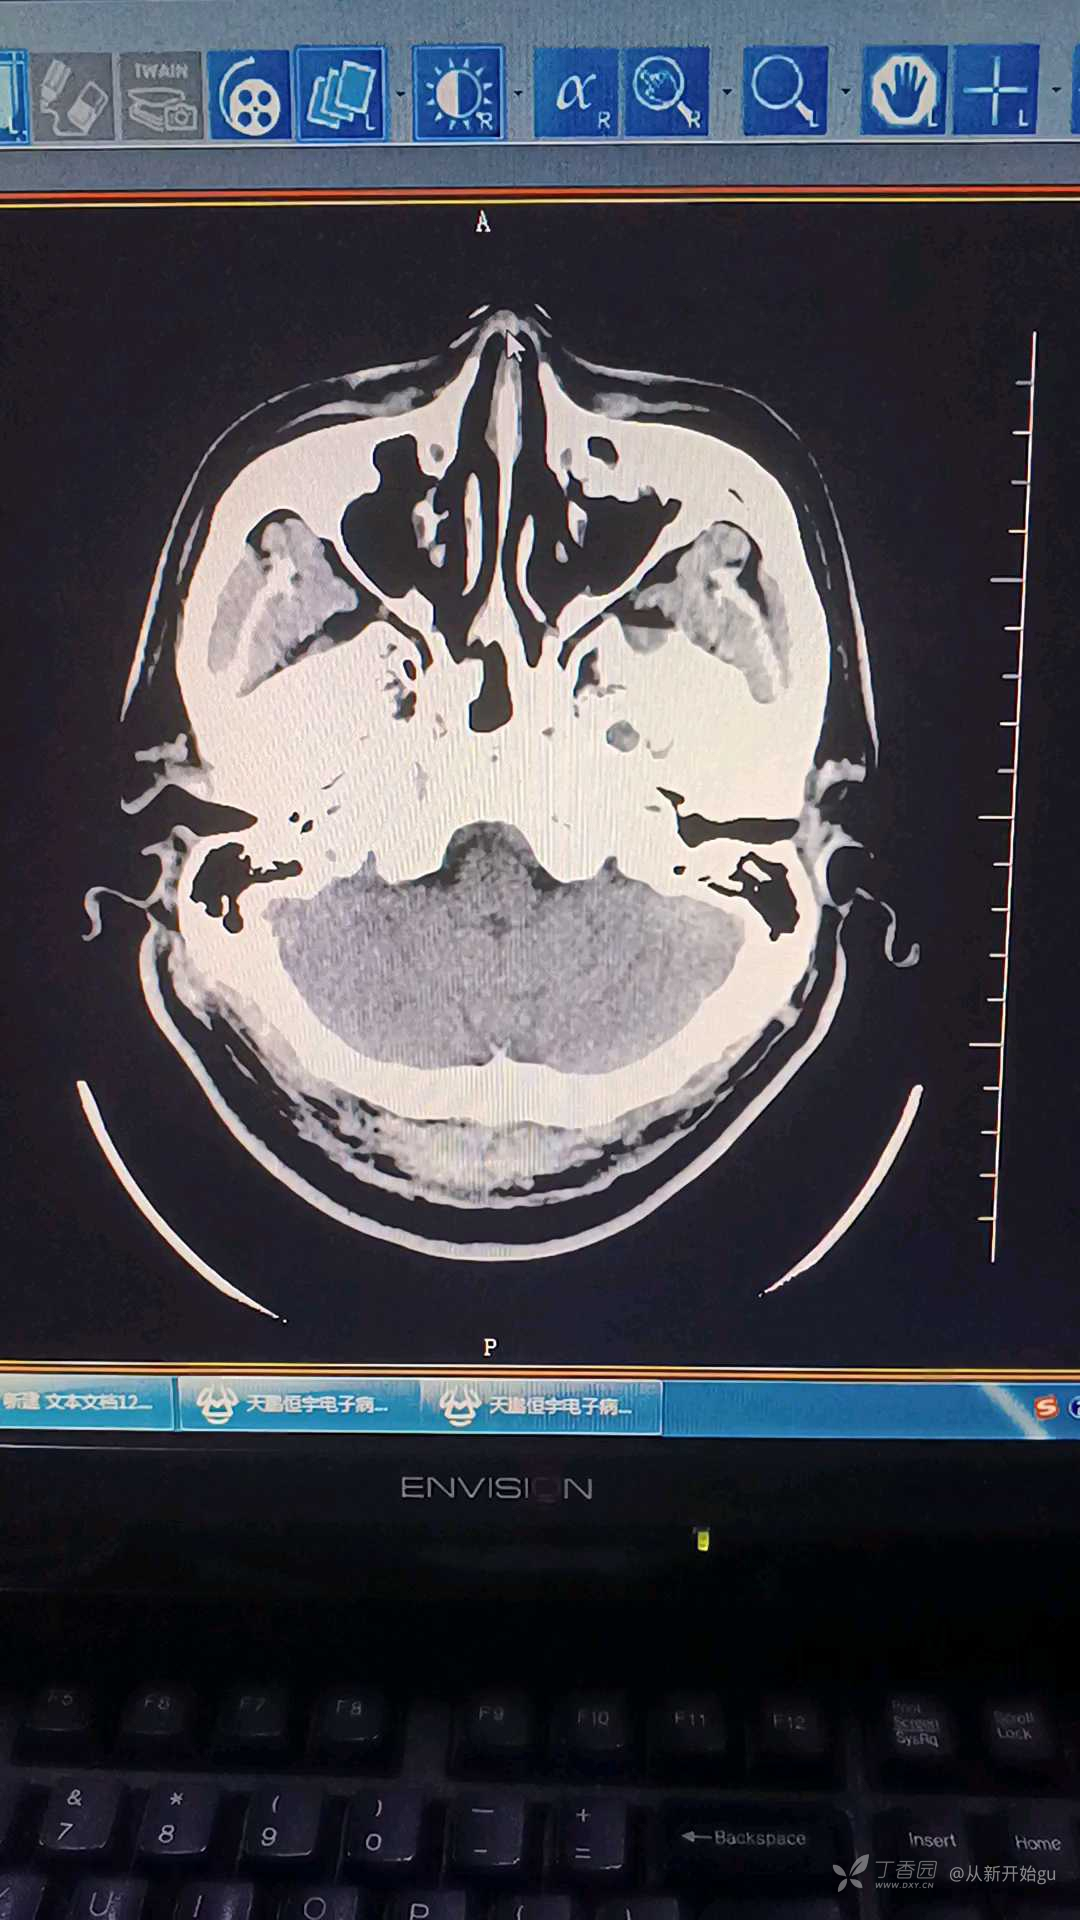

患者男,40岁,主因左下肢活动障碍1.5小时来院,既往体健。查体:左侧面舌瘫,左下肢肌力3级(入院前2级),感觉减退,巴氏征阴性。颅脑CT无明显异常。考虑患者为急性脑梗死,相关化验,血糖,凝血,血常规无异常,给予溶栓治疗。入院时心电图异常,肌钙蛋白0.041(正常值<0.04)。心电图如图所示。这个病人如果是你溶栓治疗吗?